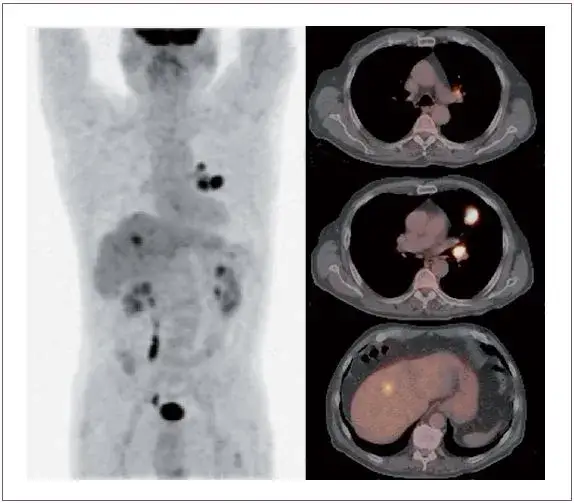

PET-CT: Najczulsza broń w wykrywaniu przerzutów

PET-CT to zaawansowane badanie, które łączy pozytonową tomografię emisyjną (PET) z tomografią komputerową (CT). Jest to niezwykle czuła metoda, która pozwala na wykrycie obszarów o wzmożonym metabolizmie cechy charakterystycznej dla komórek nowotworowych. Podczas badania podaje się pacjentowi niewielką ilość radioaktywnego znacznika (najczęściej glukozy), który gromadzi się w komórkach o wysokiej aktywności metabolicznej. PET-CT jest szczególnie cenne w ocenie zaawansowania choroby nowotworowej, poszukiwaniu nawet niewielkich przerzutów w całym ciele oraz ocenie odpowiedzi na leczenie. To prawdziwa "broń" w precyzyjnej diagnostyce onkologicznej.